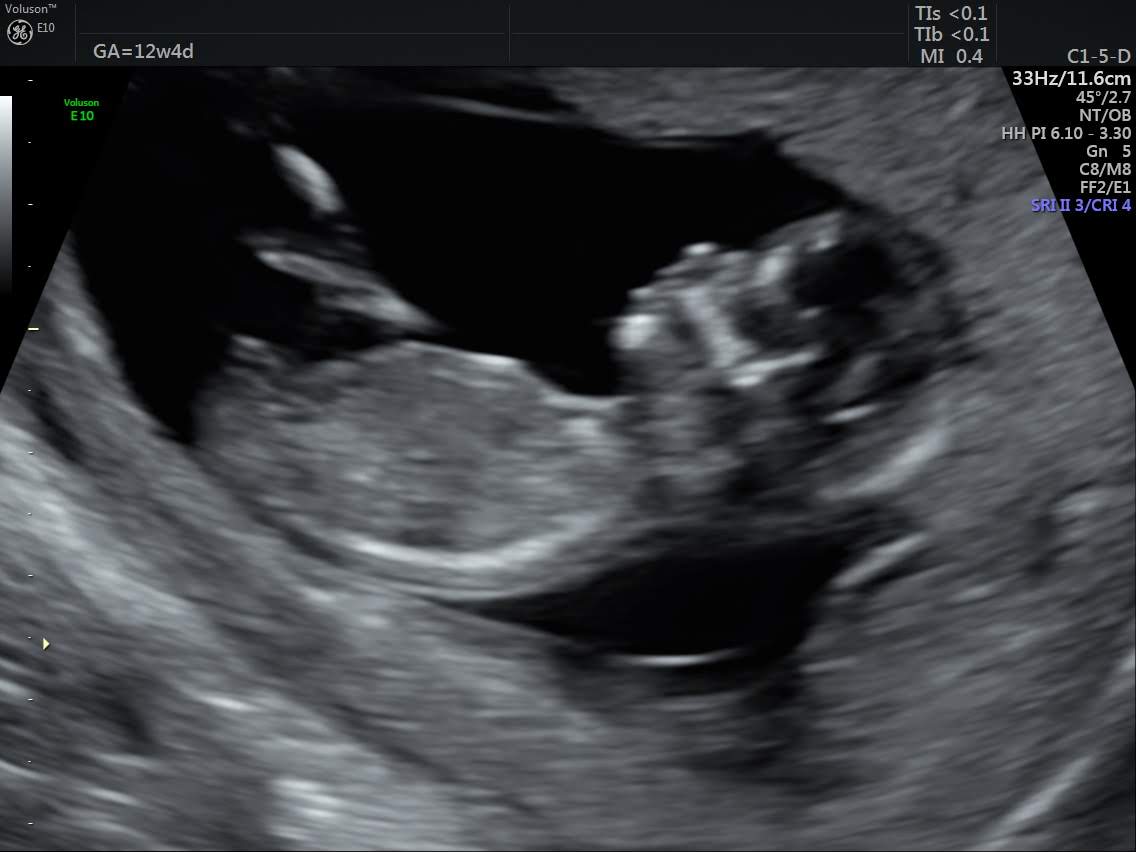

Desperate to know if this potential "nub" means I'm having a boy or girl :) All comments are greatly appreciated :D

:xy: would be my guess based on that nub.

Thinking boy due to nub inclination and looking like a stacked nub? :)